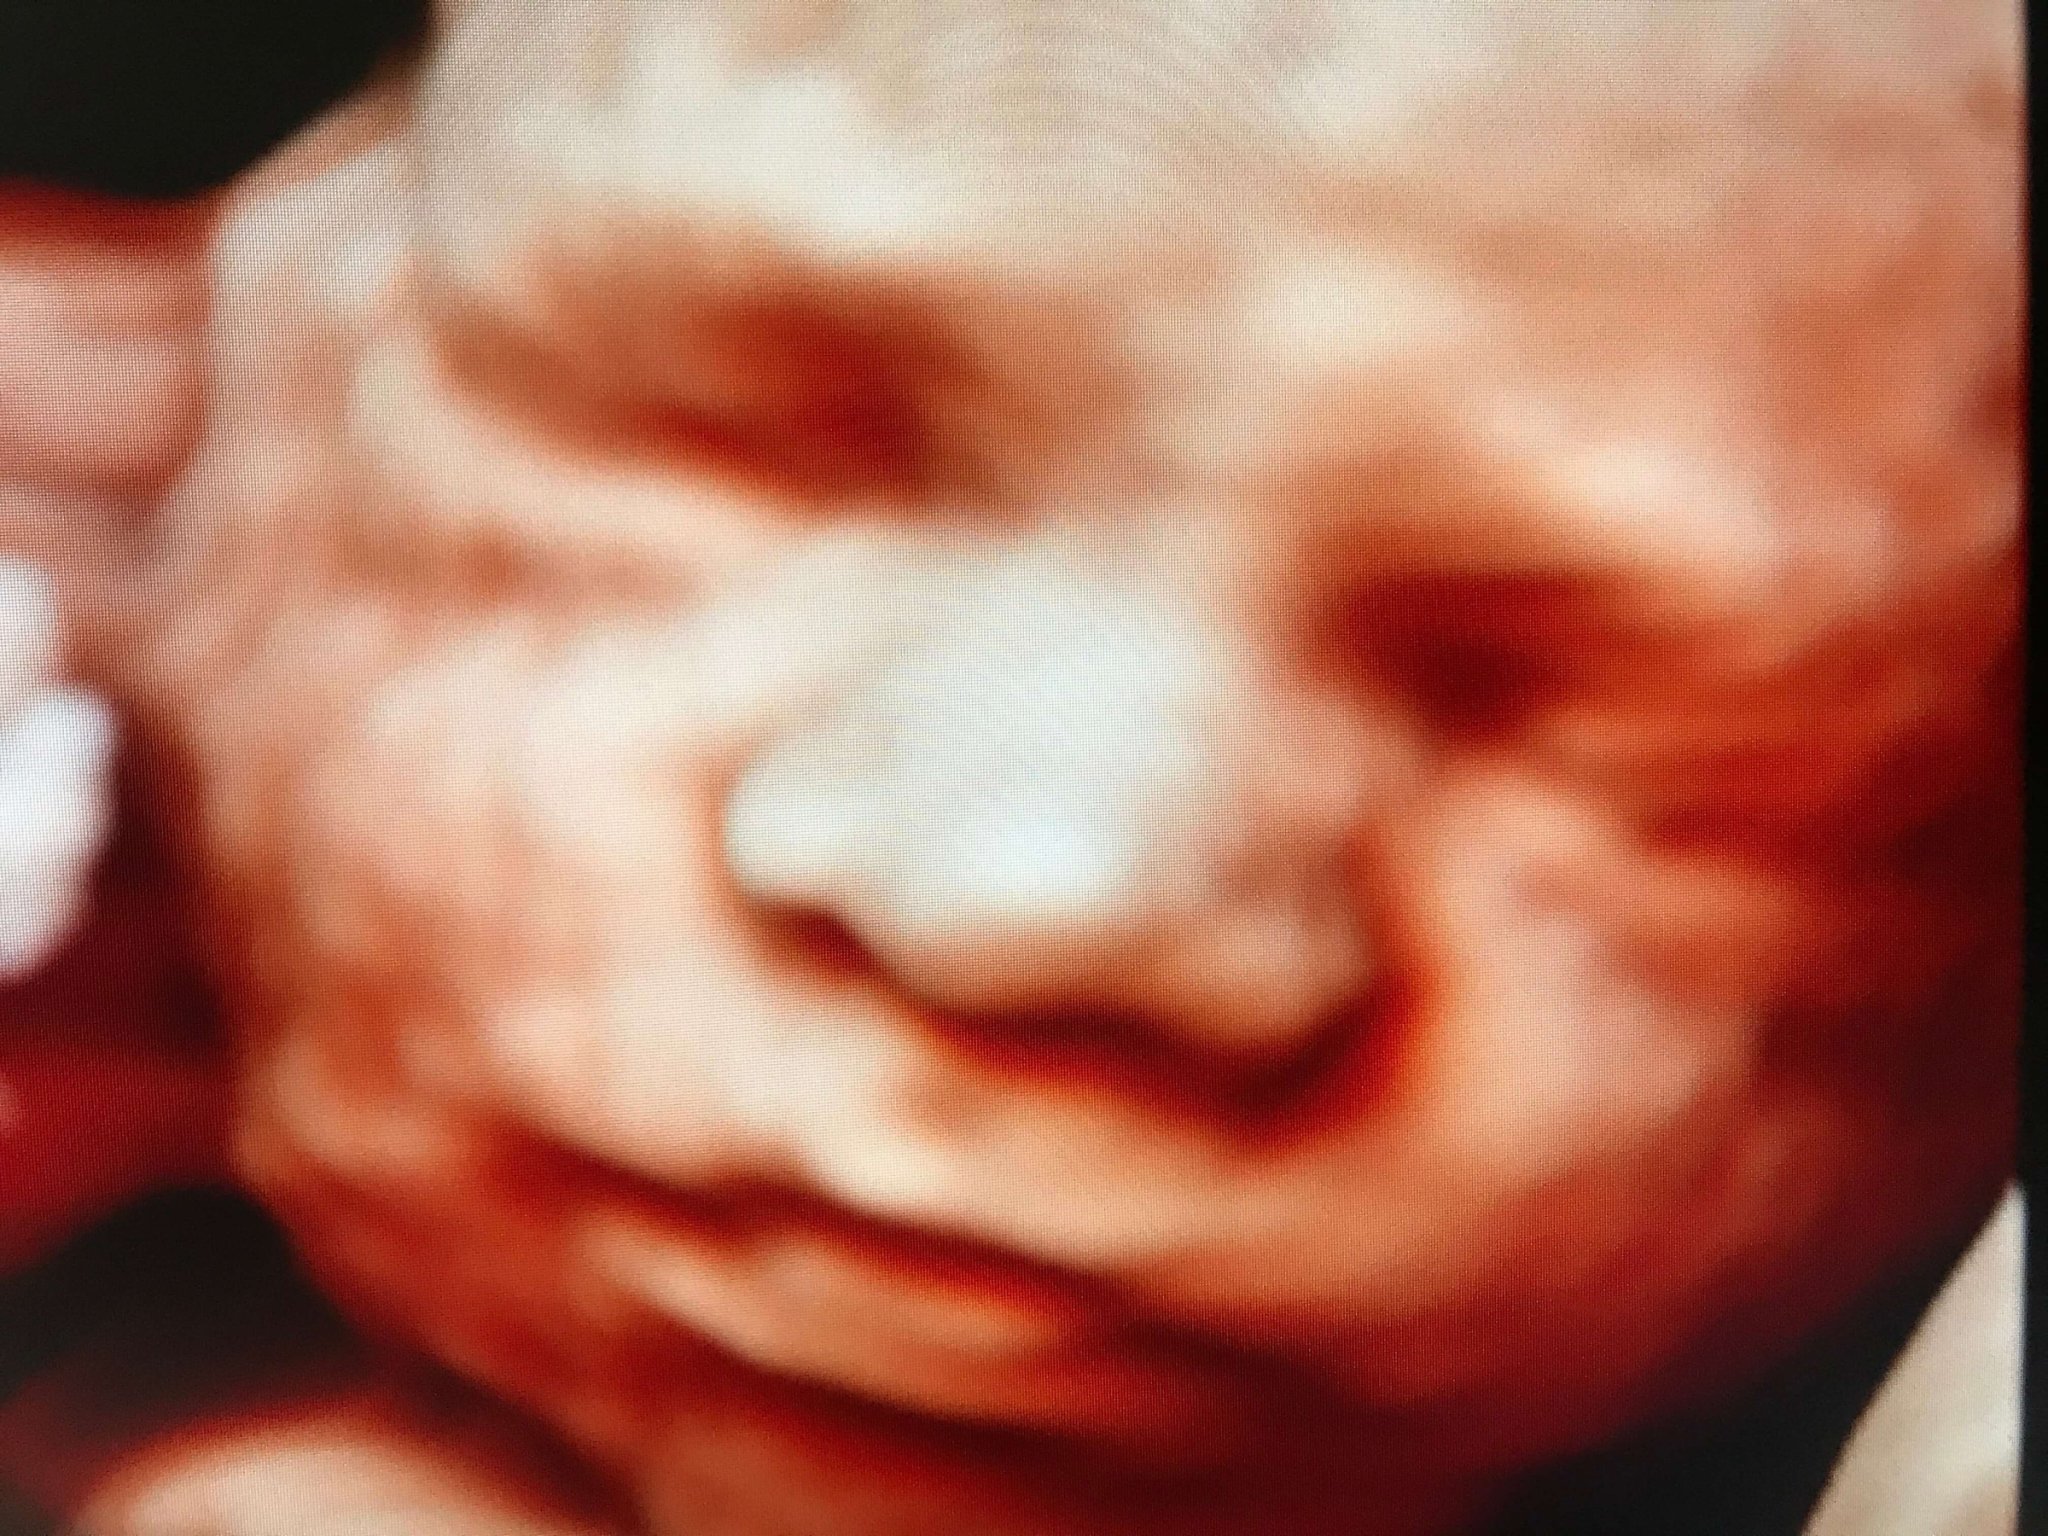

3D ultrazvukové vyšetrenie – prvý detailný pohľad na vaše bábätko

Vďaka programu Nateo Family majú mamičky možnosť absolvovať 3D ultrazvukové vyšetrenie už od 26. týždňa tehotenstva. Ak je bábätko v správnej polohe, uvidia jeho tváričku, pohyby a mimiku vo výrazne detailnejšej podobe ako pri bežnom ultrazvuku.

Pre mnohé budúce mamičky je 3D ultrazvuk silný moment. Prvý ozajstný pohľad na dieťatko, ktorý pomáha ešte viac prehĺbiť ich puto. Mnohé ocenili toto vyšetrenie ako veľmi silný moment, kedy si naplno uvedomili, že sa už čoskoro stanú mamou.

Tento zážitok bol výnimočný aj pre ich partnerov. Najmä, ak to bol ich prvý kontakt s bábätkom „tvárou v tvár“. Mnohí ho vnímali ako skutočný začiatok spoločného príbehu.